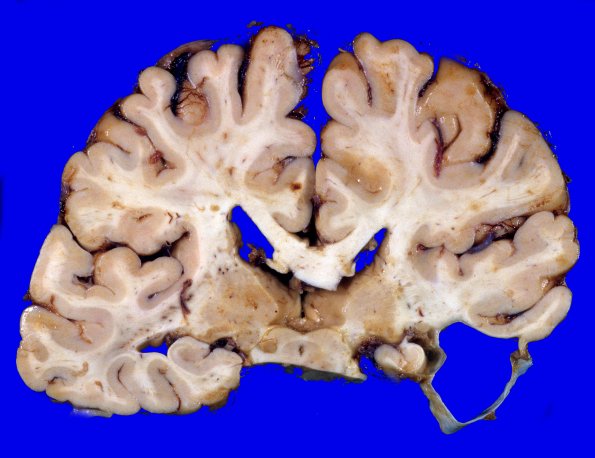

Although some arachnoid cysts typically have a benign relationship with the underlying brain, in this case there is loss of temporal cortex, the underlying white matter and atrophy of adjacent hippocampal cortex.